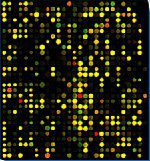

Недавно британские специалисты по биоинформатике (отрасль молекулярной биологии, занимающаяся компьютерным моделированием молекулярных процессов живых организмов) Уильям Лэнгдон и Мэтью Арно занялись исследованием так называемых человеческих ДНК-чипов. Напомню, что подобные устройства представляют собой собрание коротких последовательностей человеческой ДНК, которые являются либо участками генов, либо "техническими" последовательностями, обеспечивающими нормальную работу этих генов. Все это сборище помещено на твердую поверхность, как то: стеклянные или кремниевые компьютерные чипы, или микроскопические шарики (самые первые ДНК-чипы были вообще сделаны на подложке из фильтровальной бумаги).

Эти устройства применяются для изучения свойств генов, в частности, для выяснения, какая информация и каким именно образом считывается с конкретной последовательности ДНК, а также для моделирования мутаций. Впервые ДНК-чип был изготовлен в 1995 году, и с тех пор генетики имеют на вооружении уже несколько сотен тысяч подобных устройств. Их используют не только ученые, но и врачи — с помощью ДНК-чипов можно установить уровень активности тех или иных генов и предсказать возможность развития многих наследственных заболеваний, в том числе и аутоиммунных.

Кроме того, эти крохотные микроорганизмы, считающиеся самыми примитивными прокариотами, обладают еще одной интересной особенностью — они с легкостью встраивают свои гены в геномы любых других клеток, находящихся поблизости. Причем чаще всего внедрение происходит в "молчащий" участок чужой ДНК, то есть тот, с которого информация не считывается, это либо "техническая" зона, либо гены, считывание информации с которых по разным причинам "запрещено" самой клеткой. Компьютерное моделирование показало, что такие "пришлые" гены микоплазм могут крайне успешно сохраняться и воспроизводиться и в ДНК-чипах, то есть, in silico. Исследование же Лэнгдона и Арно подтвердило данную точку зрения.

Ученые также заметили, что обнаруженные во всех чипах "пришлые гены" являются одинаковыми, а их доля среди общего количества ДНК из чипа тоже везде стабильная — около четырех процентов. Это наводит на мысль о том, что человечество столкнулось с абсолютно новым типом "информационной инфекции". Маскируясь, воспроизводясь и адаптируясь, чужеродные "гены" прячутся и распространяются от одного чипа к другому на манер виртуальной инфекции, то есть компьютерных вирусов.

Но это еще не все. Дело в том, что каждый ДНК-чип имеет своего виртуального двойника — компьютерную базу данных, в которой записаны все последовательности ДНК, на нем в данный момент находящиеся. Само собой разумеется, что информация о генах микоплазм там тоже присутствует. Получается, что теперь все врачи, которые работают с этими базами данных, должны быть крайне осторожны, поскольку они могут поставитьнеправильный диагноз на основе анализа поведения "пришлого" гена, спутав его с исходным человеческим (как вы понимаете, визуально их различить невозможно).